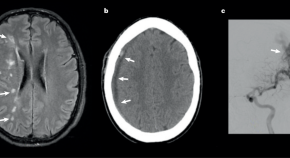

Spreading depression is a slowly propagating wave of mass depolarization that successively engulfs contiguous brain regions, causing transient neuronal hyperexcitability at its leading edge, followed by complete but reversible neuronal silence lasting minutes. Here, the authors present an evidence-based view of spreading depression as a probable cause of characteristic neurological signs and symptoms in numerous neurological conditions.